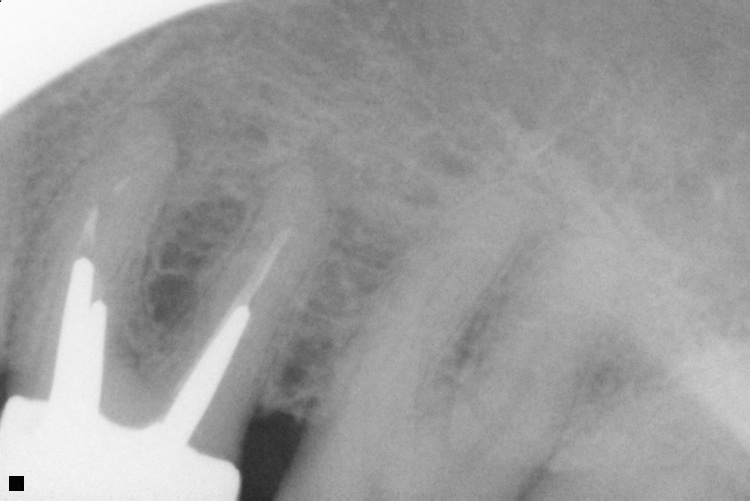

Name Last modified Size Description Parent Directory - IO000001.jpg 2020-07-28 13:36 71K IO000002.jpg 2020-07-28 13:36 88K IO000003.jpg 2020-07-28 13:36 82K IO000004.jpg 2020-07-28 13:36 85K